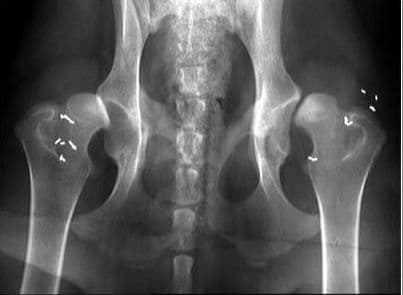

Viêm cột sống dính khớp biến chứng thế nào?

Hầu hết người mắc viêm cột sống dính khớp đều phát hiện muộn khi đã có nhiều biến chứng. Không ít người bệnh bị tàn phế từ khi còn rất trẻ. 1. Viêm cột sống dính khớp là bệnh thế nào? Viêm cột sống dính khớp là tình trạng viêm mạn tính, biểu hiện đặc […]